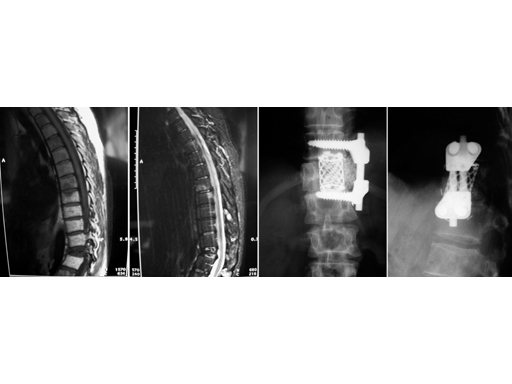

39-year-old woman, pathological fracture in L1 due to metastasis of breast cancer. Synmesh combined with Ventrofix.

SynMesh is used for vertebral body replacement in the case of tumor or trauma from T1L5. Existing sizes are cut to fit in corpectomy sites, which increases OR time. Straight implants in longer vertebral body reconstructions can impinge posteriorly on the spinal cord because they do not follow the normal anatomy. Therefore, additional heights have been developed to reduce the need to cut down larger sizes and reduce OR time in these cases. The 10 mm diameter SynMesh is now available in heights of 14, 16, 20, 22, 24, and 32 mm, the 12 mm diameter in heights of 14, 16, 20, 22, and 24 mm, and the 15 mm diameter in heights of 18, 20, 22, and 24 mm. Contoured implants are offered to better fit the anatomy and reduce the likelihood of impingement on the spinal cord. They are available in diameters 12 mm, 15 mm, 17 x 22 mm, 22 x 28 mm, and 26 x 33 mm. The available heights for all diameters are 88 mm and 150 mm.

The SynMesh system is indicated for use as a vertebral body replacement device in thoracolumbar spine (T1 through L5) to replace a collapsed, damaged, or unstable vertebral body due to tumor or trauma. This modular system allows building of the most appropriate construct to address the defect and patients anatomy. The SynMesh system is to be used with Synthes supplemental internal fixation systems, eg, VentroFix or USS.